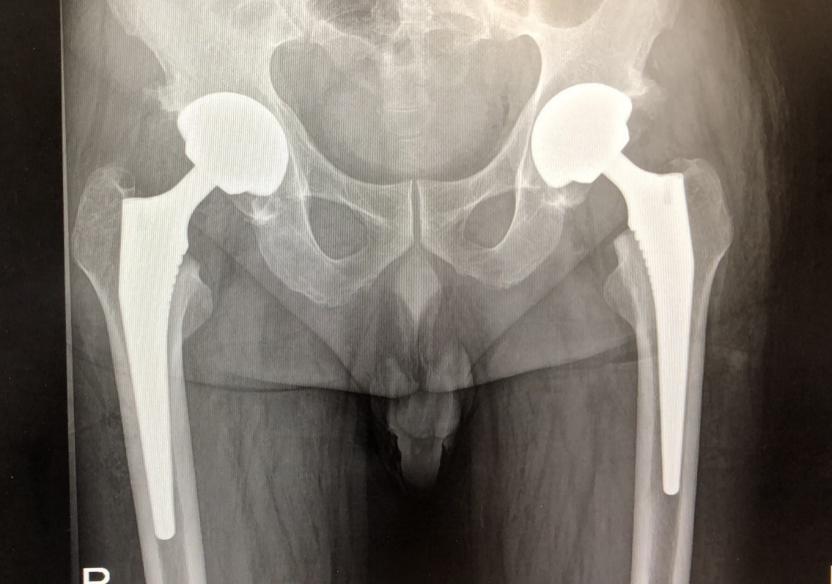

合肥京东方医院骨科周建生团队完成双侧全髋关节置换术

5月7日,合肥京东方医院骨科特聘首席专家周建生教授带领团队成功实施了一例双侧全髋关节置换术,三天后,饱受病痛折磨20年的王先生在医护的搀扶下迈出了康复的“第一步”,对医院和医生的感激之情溢于言表:“我的双髋部疼痛20多年了,现在终于能好好走路了”。

20年前,王先生双侧髋关节出现疼痛,当时疼痛较轻,便没有加以重视,后来症状逐渐加重,多年来一直忍受着疼痛的折磨。1个月前,王先生自觉疼痛症状加重无法行走,严重影响日常生活,无奈之下前往当地医院检查,摄片提示双侧股骨头坏死,为寻求进一步治疗,患者多方打听转至我院骨科就诊。

接诊后,我院骨科团队迅速为王先生完善了相关检查,最终以“双侧股骨头无菌性坏死”将其收入住院治疗。

周建生教授带领骨科团队对王先生的诊疗方案进行了详细的分析讨论,在充分评估患者病情、术中风险、术后管理难度及患者术后恢复情况后,决定为其行双侧全髋关节置换术。

凭借丰富的临床经验及熟练精准的手术技巧,周建生教授迅速将已经坏死严重的股骨头取出,去除髋臼周围增生的骨赘,打磨髋臼,将髋臼假体置入患者髋臼。同时处理股骨近端,髓腔锉扩髓,安放合适的股骨头假体,确认股骨头包容良好,髋关节松紧适宜,复位髋关节,术中测试髋关节活动良好。在一侧手术完成后,立即调整体位,对另一侧的髋关节进行置换。整个手术步步分明、衔接流畅、2小时内顺利结束,最大程度减少了臀部肌群的离断,缩短了手术时间,减少了术中出血量,极大地减轻了手术为患者带来的创伤,也一定程度上减少了患者的住院时长和诊疗费用。

在医护人员的精心照护下,王先生恢复情况良好,术后几日便可下地行走。

该例双侧全髋关节置换术的开展,标志着我院关节置换技术成功迈向新的高度,也为众多股骨头坏死患者提高生活质量、重回健康带来了希望。